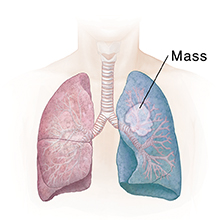

| Pneumonectomy removes the entire lung. |

A lung mass or tumor

If a tumor has been found in the lung, a tissue sample (biopsy) can be removed. This piece of abnormal tissue is tested in a lab to find out if the growth is not cancer (benign) or is cancer (malignant). The tissue near the tumor can also be examined to see if the tumor has spread. If the tumor needs to be removed, its size, location, and spread determine how much of the nearby lung also needs to be removed. Removing part or all of a lung is called a lung resection.